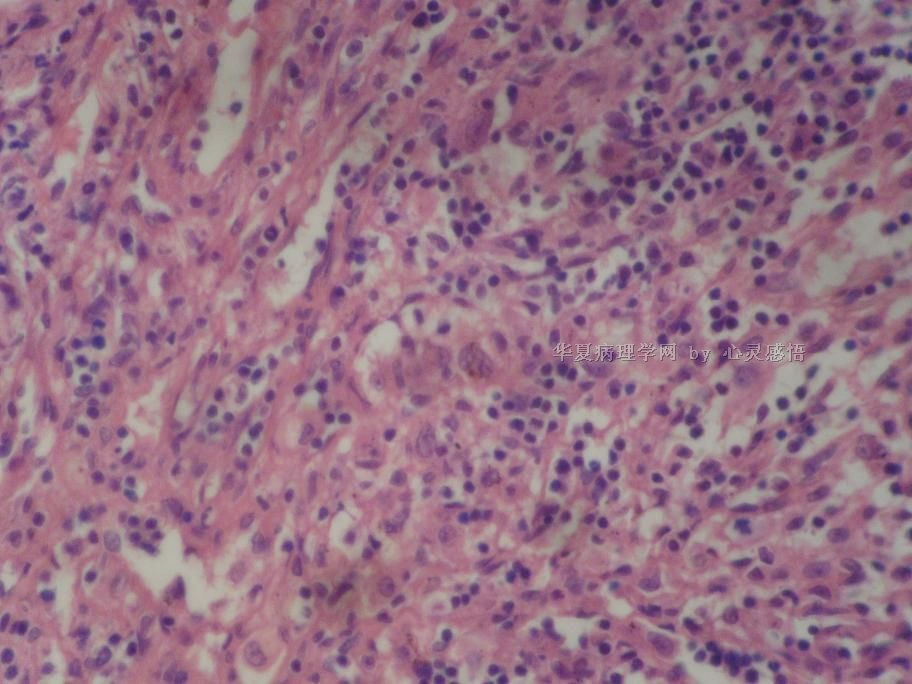

• 食道癌,淋巴结有没有转移,谢谢。图3

图3

1-6图是鳞癌。7-22图片无癌。

淋巴结没有转移

本帖最后由 于 2010-11-17 20:19:00 编辑  图14,19有转移

没有转移。

请教楼主;图片19是淋巴结吗?如果是应该是有癌转移!

没有转移,食道旁的淋巴结和肺旁的淋巴结相似,含有吞噬细胞。